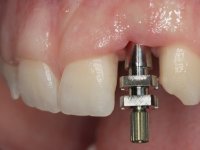

An impression was made on the implant with open tray technique using soft and regular consistency putty. At the laboratory, after confection of the work model, a diagnostic waxing was performed, which sought to find an aesthetic compromise solution. In this sense, a temporary workpiece screwed onto the implant was used to simulate the difficulties we would have with screwing the definitive work. This study abutment consisted of wax to reproduce soft and hard tissues, seeking to anticipate the use of ceramics of gingival and coronary shade. Also, part of the interproximal papillae corresponding to the distal portion of the 2.1 tooth and the mesial tooth of the tooth 2.3 were also waxed, anticipating the use of composite resin “chips” with gingival tonality. Finally, a veneer was waxed to correct the microdontia of the tooth 1.2. In this waxing, the vestibular emergence of the orifice for access to the screw of the implant abutment was evident. Once this therapeutic option was accepted, the implant abutment in polymerized composite resin was prepared at the lab, as well as the papillary "chips", also in composite resin of gingival tonality. Tested in the mouth, the abutment was screwed and the "chips" bonded. The access hole of the screw was filled with composite resin. In subsequent consultation, a gingivectomy was performed on the cervical contour of teeth 1.3, 1.2 and 1.1 with the aim of correcting the asymmetry between the first and second quadrant. After the soft tissues were cicatrized, a dental bleaching was performed according to the patient’s aesthetic requirements. Final impression on the implant was made using the silicone open tray technique, taking care to individualize the transfer piece by copying the emergence profile of the patient’s provisional abutment. At the laboratory, the impression yielded a definitive working model, on which the abutment was waxed on a plastic insert. This process was carried out with the orientation of a wall of silicone based on diagnostic waxing. The wax made on the plastic part was placed in a special holder that allowed its scanning in a laboratory scanner. This scan by CAD process informed the design of an abutment in Zr. later materialized by a CAM process. The Zr. abutment was tested in the mouth, validating its clinical and imaging establishment. During this consultation, the choice of color was made by the ceramist, of both the coronary ceramics and the ceramic of gingival tonality to be used. Individualized color scales were used. At the laboratory, the coronary and gingival ceramics were placed on the implant abutment and later, on a working model with refractory gypsum, a veneer of feldspathic ceramic was made. This veneer was built on a surface specially designed for this purpose in the abutment. This surface tried to reproduce a dental preparation performed for the same effect. In the mouth the abutment was screwed with a torque of 35N, the access hole to the screw was filled with Teflon and later filled with composite resin. The veneer was bonded onto the implant abutment using the conventional bonding technique, with relative insulation. For economic reasons, the patient did not proceed to perform the veneer on tooth 1.2. Although a limited aesthetic compromise was expected from the outset, a result was achieved which satisfied the patient.